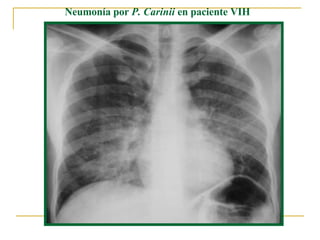

Neumonía por  P. Carinii  en paciente VIH

Paciente VIH positivo con neumonía por  Pneumocytis carinii  (fase subaguda o en resolución)

Neumonía por  Pneumocystitis carinii.  Patrón pulmonar intersticial bilateral.